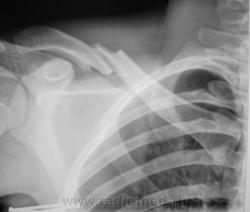

если так наступит консолидация ключицы, то нарушение функции верхней конечности не будет т.к смещения по длинне практически нет, но у взрослого человека удержать, в таком положении, повязками невозможно, мы таких больных оперируем. на рентгенограммах похоже подросток, и возможно смещение по ширине, выбор тактики за хирургом.

Конечно - без дополнительных укладок решить вопрос о смещении вперед-назад нереально, а это важно; очень "понравилась" гематома по верхнеиу краю внутреннего отломка; несколько смущает очаговая (или придираюсь) тень в первом межреберье.....

Подросток - 15 лет.

Консолидация тут в весьма туманном будущем. Наши травматологи сколько раз подобное творили, срасталось ну оооочень долго.